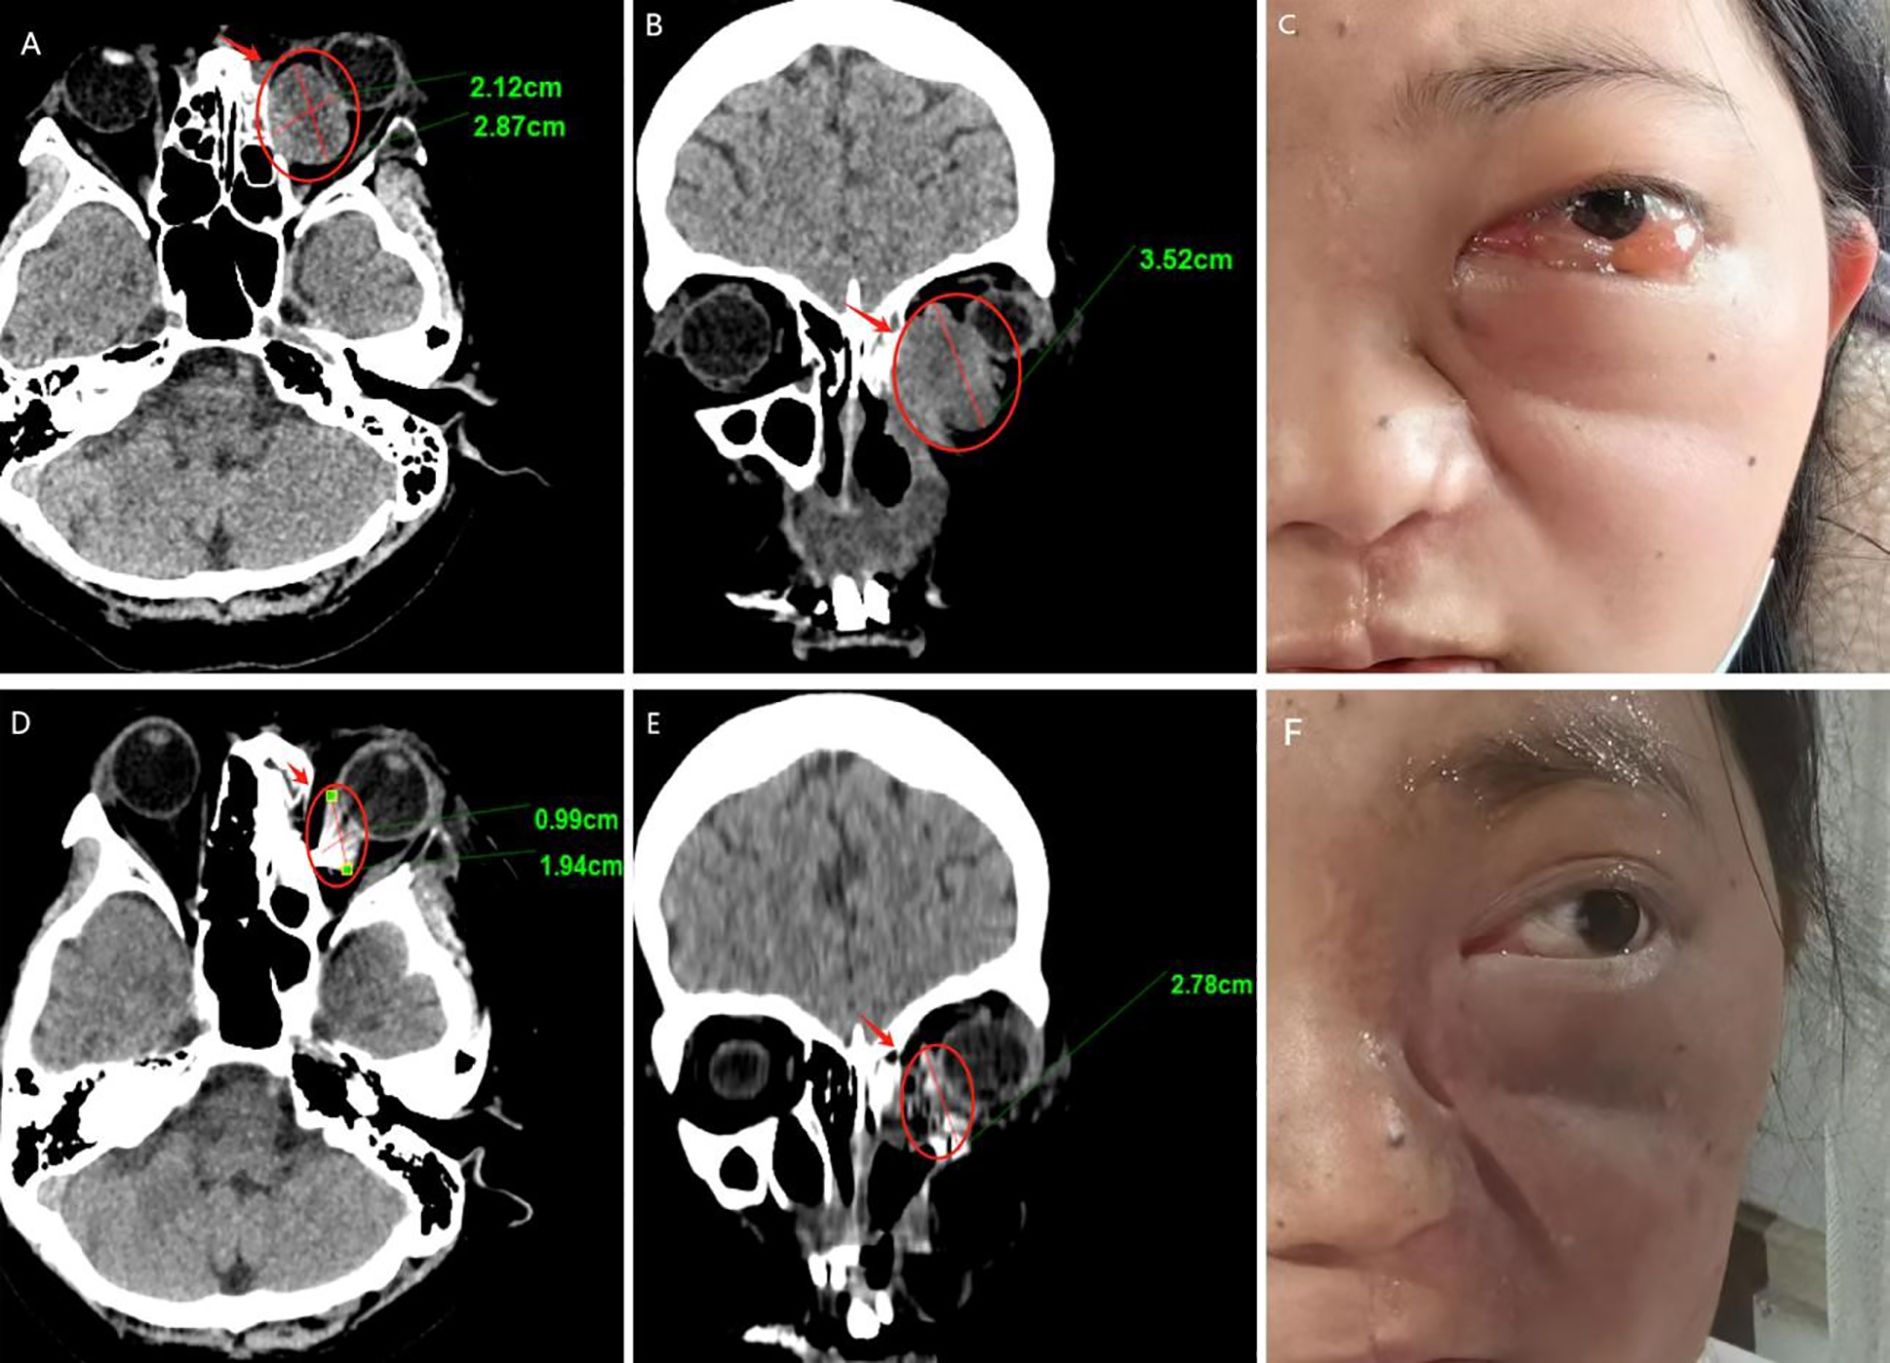

We followed up with the patient at 1 month, 3 months, 6 months, and 1 year postoperatively. After one year of follow-up, the volume of the primary tumor significantly decreased (the tumor size was approximately 5.57×4.04×6.35 cm before treatment, and 2.32×0.96×3.15 cm after treatment) (Figure 5). The intraorbital tumor decreased in size from 2.87×2.12×3.52 cm to 1.94×0.99×2.78 cm.The compression of the optic nerve by the tumor was alleviated, and both visual field and vision showed signs of recovery. The proptosis of the eyeball was significantly improved. The swelling and deformity of the eye were markedly improved, resulting in a more natural facial appearance (Figure 6). The patient’s visual acuity improved significantly from 20/200 (LogMAR 1.0) preoperatively to 20/30 (LogMAR 0.2) at 1 year postoperatively. The patient’s quality of life was significantly enhanced. No complications such as radiation-induced cataracts, optic neuropathy, or cerebral edema were observed during the last follow-up in March 2025.

Figure 6. Follow-up results (A–C) Pre-therapeutic imaging series, (D–F) Post-therapeutic imaging series (12-month follow-up) (A, D) CT axial views, (B, E) CT coronal views.